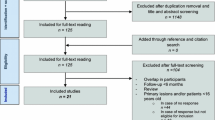

A search of three major databases yielded a total of 297 studies (77 in Pubmed, 106 in Embase, and 144 in Web of Science). The exclusion process was conducted using Endnote20 software to remove 140 duplicate studies. Two investigators independently screened the remaining 157 articles by reviewing titles and abstracts, resulting in the exclusion of 103 irrelevant studies. Subsequently, the remaining 54 articles were assessed for full-text availability. Among them, five studies could not be obtained for full text, while another 28 studies were excluded based on the predefined inclusion and exclusion criteria. Additionally, four studies were identified as duplicates and two were not written in English. Finally, a total of fifteen eligible studies were included in the meta-analysis. The screening flow chart is in Fig. 1.